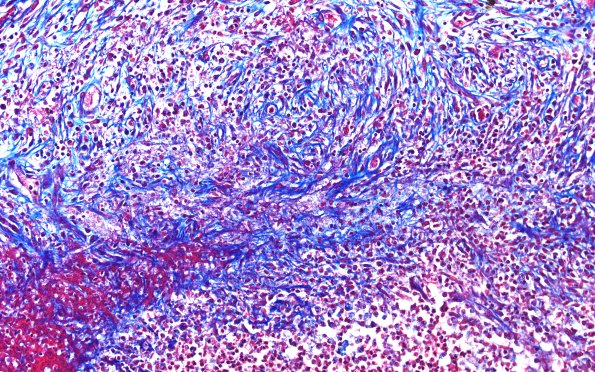

17F3 Abscess A (Case 17) N12 TRI 20X

The intermediate zone is rich in collagen and fibroblasts. (Trichrome)